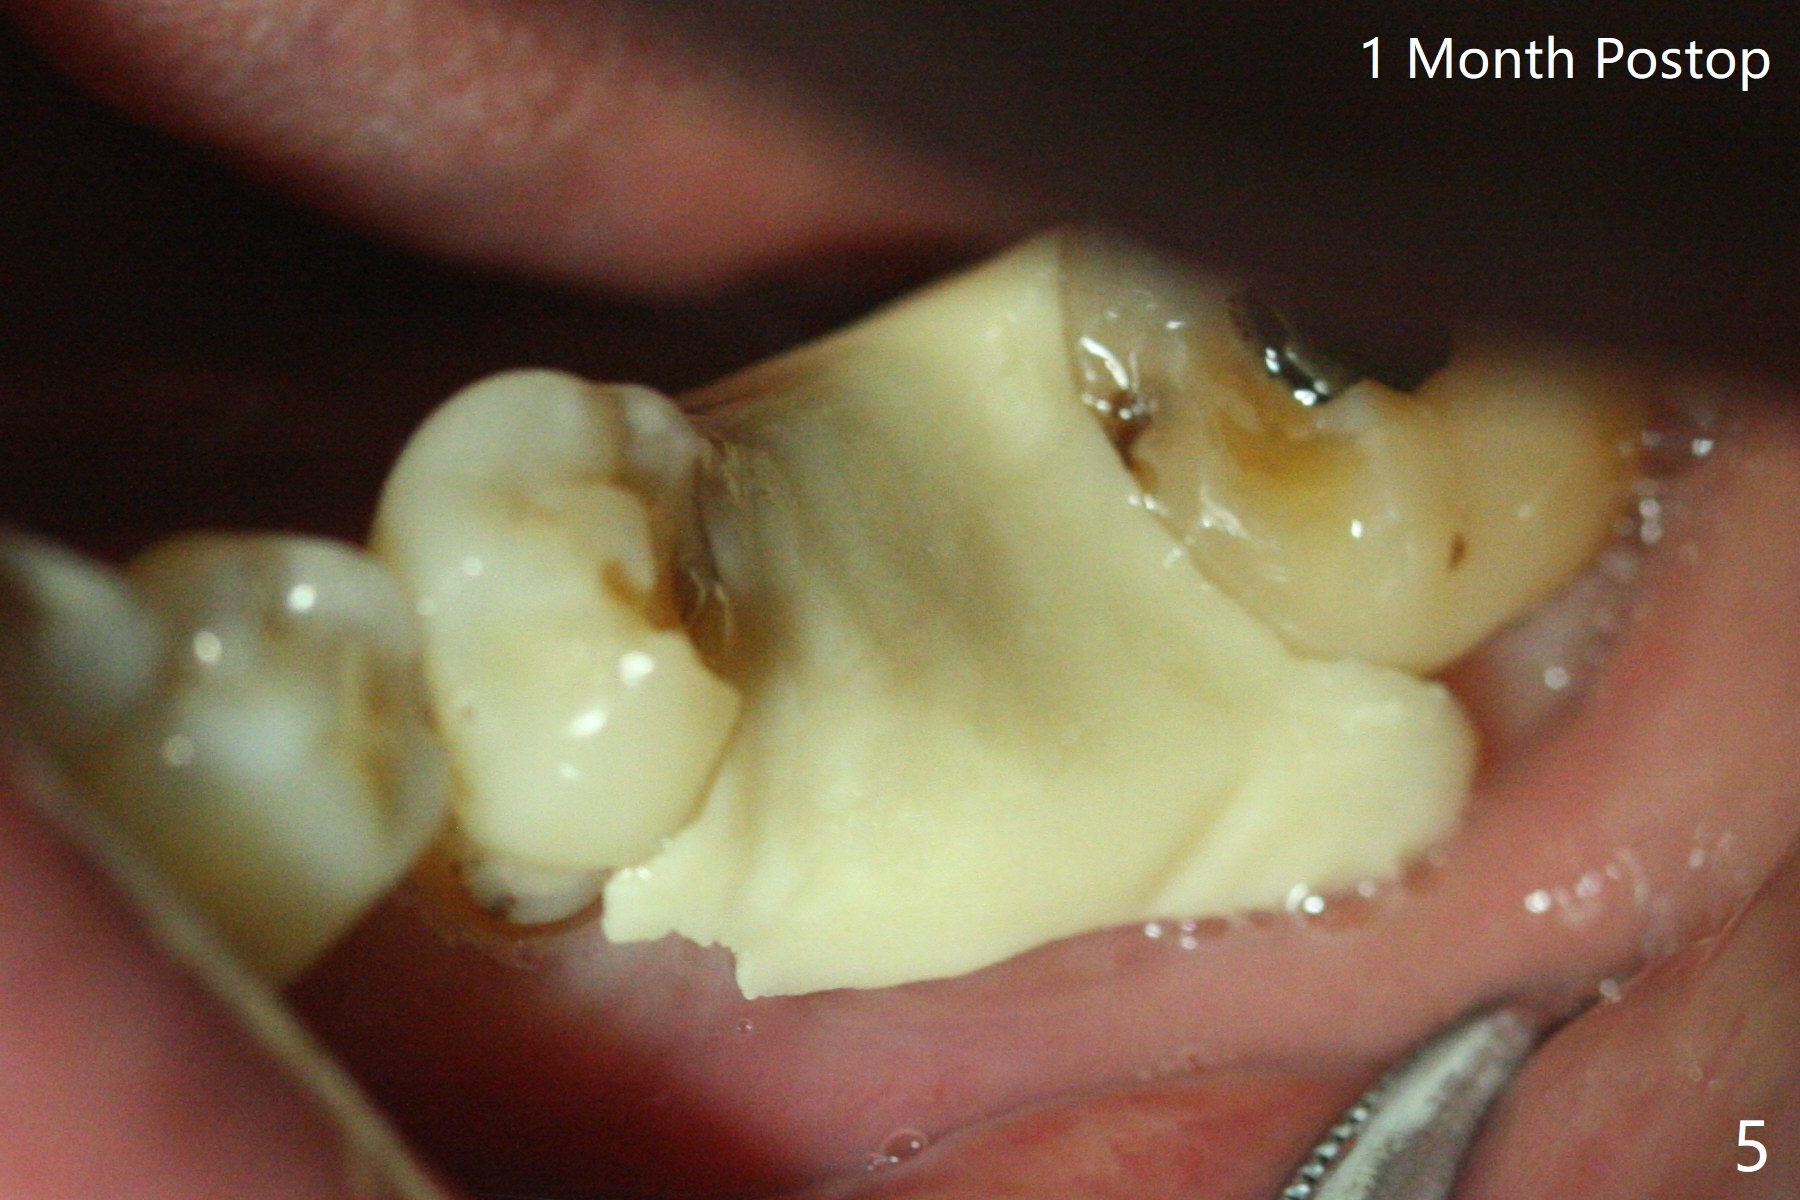

A 73-year-old man (with history of lung cancer with chemotherapy 6 years ago) requests removing the tooth #19 (Fig.1) with the loose mesiolingual fragment (Fig.2 ML). The mesiobuccal plate is low when the tooth is extracted. The septum should provide additional blood supply to bone graft to facilitate healing (Fig.3 S, as compared to the case without it). After placement of 6-month membrane and suturing, acrylic dressing is applied, which is stable 9 days postop (Fig.4 A). The acrylic dressing remains in place 1 month postop (Fig.5). After wiggling, it dislodges fairly easily. The socket heals with slight atrophy (Fig.6).